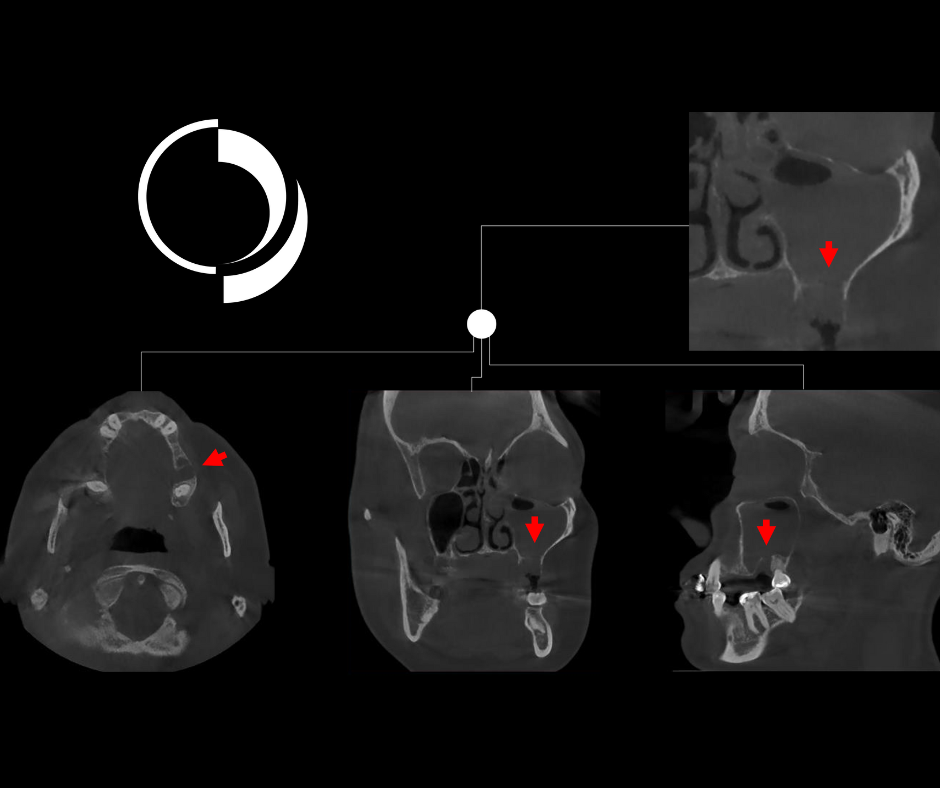

Cortes axiales más superiores que los anteriores donde se puede identificar claramente que las celdillas etmoidales anteriores y medias del lado izquierdo ocupadas de contenido isodenso.

Al hacer barrido mediante cortes coronales de anterior a posterior es evidente seno maxilar izquierdo ocupado con contenido isodenso, en contraste lado derecho permeable.

Cortes coronales más posteriores que los anteriores donde podemos identificar que el contenido isodenso del seno maxilar izquierdo es parcial.

En los cortes coronales más posteriores que los anteriores evidenciamos la comunicación del seno maxilar con el meato medio del lado izquierdo, la relación con el cornete medio y el compromiso del complejo osteomeatal del lado izquierdo, contrastando con la permeabilidad en el lado derecho

En las vistas transaxiales se ilustra la comunicación bucosinusal, solución de continuidad de la basal antral, sin evidencia de cuerpos extraños.

Corte transaxial que muestra la solución de continuidad de la basal antral.

Cortes multiplanares que nos evidencian la solución de continuidad de la basal antral, el ocupamiento del seno maxilar izquierdo comparado con la permeabilidad contralateral y la comunicación buco sinusal.